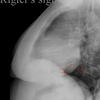

Rigler's sign

to assess LV size